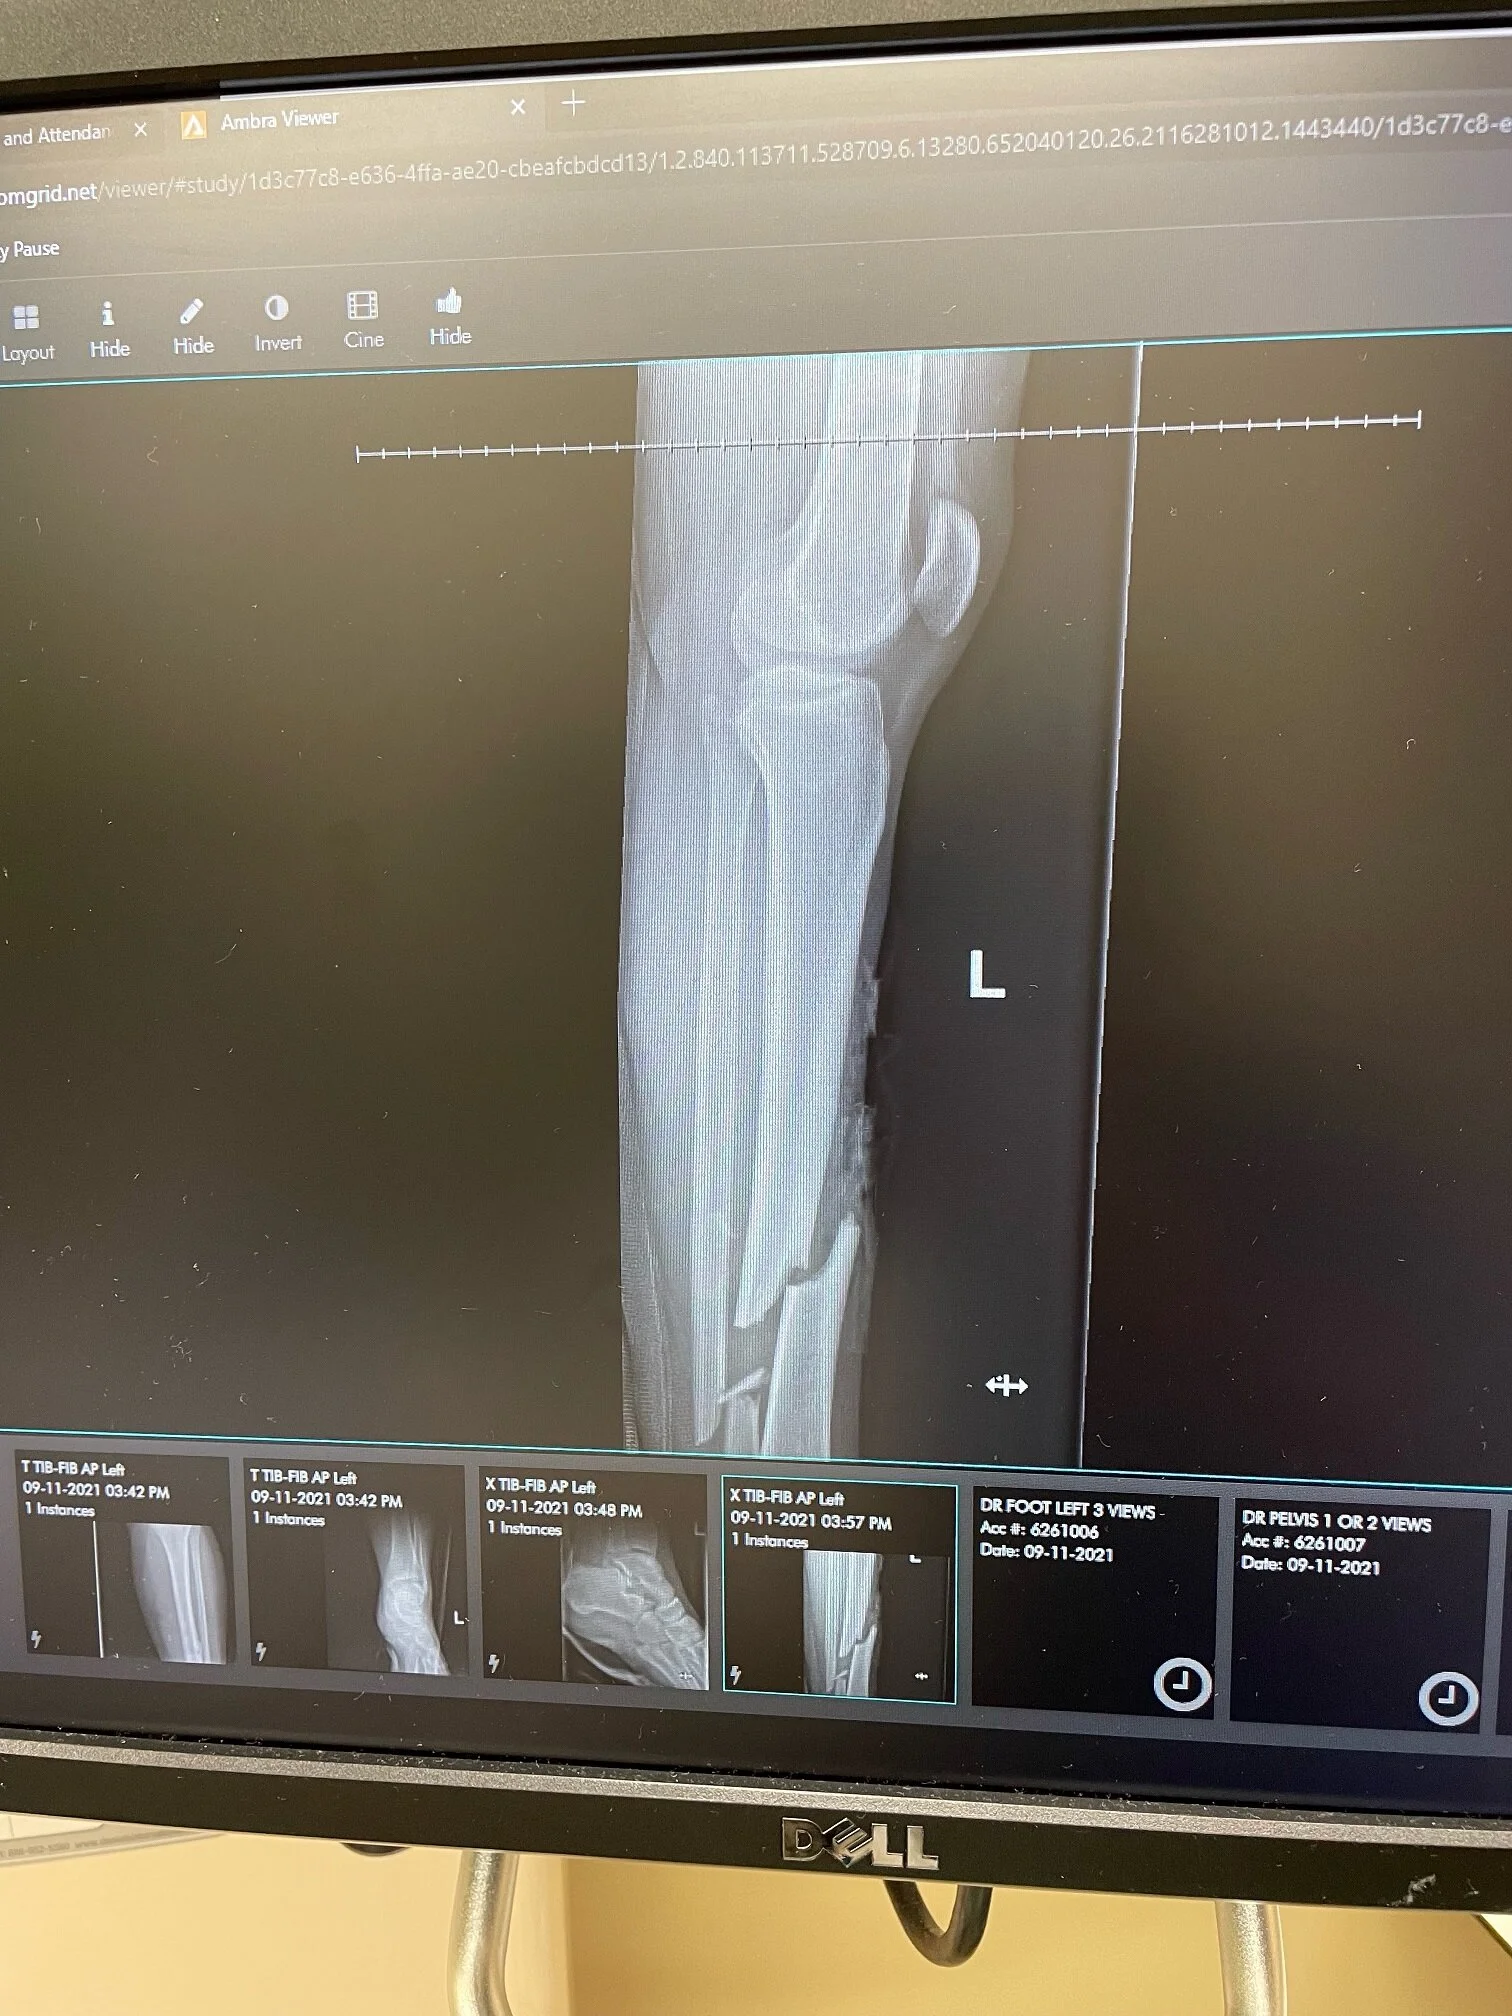

The Cannonball is a very difficult and dangerous event. One of the first casualties was yesterday. #110 Brianna Meisinger in one of the youngest riders we have. This is her first Cannonball, and she is riding a 1929 Indian Scout. She was involved in an accident that ended up sending her to the hospital. The photo below is the Xray of her leg. The rumor is that she is doing well, and we may see her before the Cannonball is over.